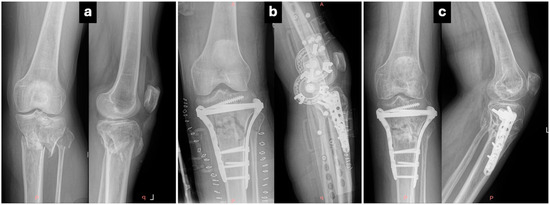

Comparative Outcomes of Single- Versus Dual-Incision Approaches for Open Reduction and Internal Fixation of Complex Tibial Plateau Fractures

Background/Objectives: Open reduction and internal fixation with plates and screws is the treatment of choice for bicondylar tibial plateau fractures. The use of a surgical approach remains a topic of debate regarding the site and number of incisions that ensure best access [...] Read more.

Background/Objectives: Open reduction and internal fixation with plates and screws is the treatment of choice for bicondylar tibial plateau fractures. The use of a surgical approach remains a topic of debate regarding the site and number of incisions that ensure best access for reduction with minimum additional soft tissue damage. This retrospective cohort study compared clinical, radiological, and functional outcomes of single- (anterior) versus dual-incision (anterolateral and medial) approaches that are widely used in the operative treatment of Schatzker V–VI tibial plateau fractures. Methods: Eighty-two patients treated between 2005 and 2020 were retrospectively analyzed. Fifty-two underwent a single-incision (SI) approach and 30 a dual-incision (DI) approach. Operative parameters, complications, reduction quality, Knee Society Score (KSS), Oxford Knee Score (OKS), and post-traumatic arthritis incidence were assessed. Results: Mean patient age was 50.6 years, with a mean follow-up of 8.5 years. Operative time was shorter in the SI group, though fluoroscopy time was longer. No significant difference was observed in reduction quality or wound complications. Post-traumatic arthritis occurred in 57.6% of SI and 53.3% of DI patients, with severe arthritis more frequent in SI (30% vs. 12.5%, p < 0.05). Seven patients required conversion to total knee arthroplasty (five SI, two DI). Functional recovery was similar: mean KSS 68.6% (SI) vs. 70.5% (DI) and OKS 36.1 vs. 40.8 (p > 0.05) at 5 years. Conclusions: Both single- and dual-incision approaches for complex tibial plateau fractures provide satisfactory long-term outcomes. While differences in complications and arthritis rates were minor, surgical choice should be guided by the fracture morphology, patient characteristics, and surgeon’s experience to balance reduction quality with soft tissue preservation. Full article

Figure 1